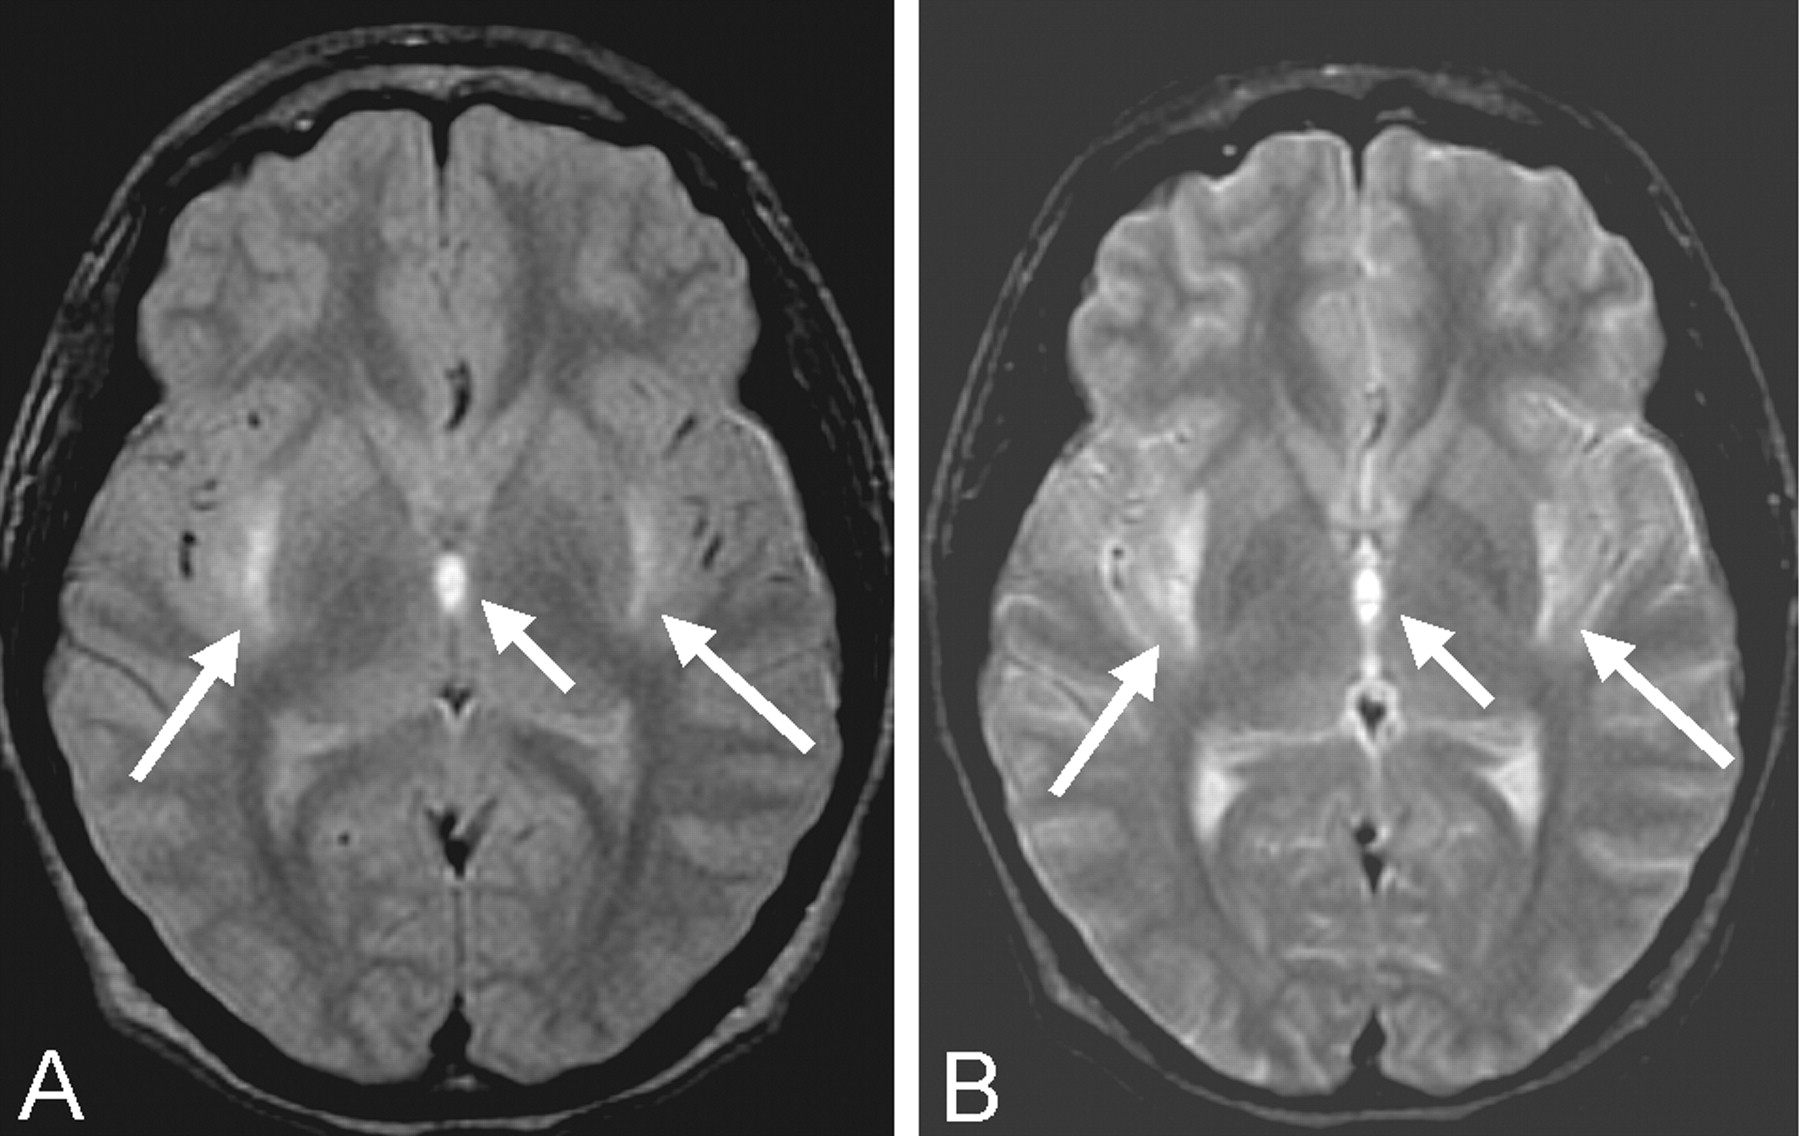

MR imaging of the brain was therefore performed. Proton density–and T2-weighted images revealed hyperintensity of the external capsules and adjacent lateral putamen, the paraventricular nucleus of the thalamus, and scattered areas throughout the cerebellar hemispheres (Fig 1). Pre- and postcontrast T1-weighted images demonstrated T1 shortening and accompanying enhancement only in the supratentorial lesions (Fig 2). T1 shortening in the paraventricular nucleus of the thalamus bordering the third ventricle also extended into the third ventricle, suggesting an underlying hemorrhagic cause, resulting from extracellular methemaglobin (Fig 2). Areas of T2-weighted changes in the cerebellum had corresponding darkness on T1-weighted images but were also noted to enhance after contrast medium administration (Fig 3). These findings suggest an ischemic and hemorrhagic small vessel process, both supra- and infratentorial.

Proton density–(A) and T2-weighted (B) axial MR images of the brain at the level of the third ventricle show hyperintensity (arrows) in the external capsules and medial thalami and altered signal intensity in the adjacent third ventricle.

Although heat can affect all organ systems adversely, it is known that the cerebellum is especially susceptible (1). The Purkinje cells within the cerebellum are, in particular, vulnerable to thermal injury. As noted above, it has been suggested the hyperthermia itself, as opposed to the resultant hypoxic or ischemic insults, causes the destruction of Purkinje cells (1, 6). This neuronal destruction then causes generalized cerebellar atrophy, which has been widely reported as evidenced by MR imaging (1, 3, 7); however, to our knowledge no reports of bilateral signal intensity alterations and enhancement of the cerebellum exist in the literature. This suggests that, in addition to the likely ischemic and hemorrhagic small vessel process seen supratentorially, we are also seeing it infratentorially. Hyperintensity on both T1- and T2-weighted images of the cerebrospinal spaces of the third ventricle also suggests an ischemic and hemorrhagic mechanism, implying spread of intracellular methemoglobin into the third ventricle from adjacent hemorrhagic infarction (Figs 1 and 2).